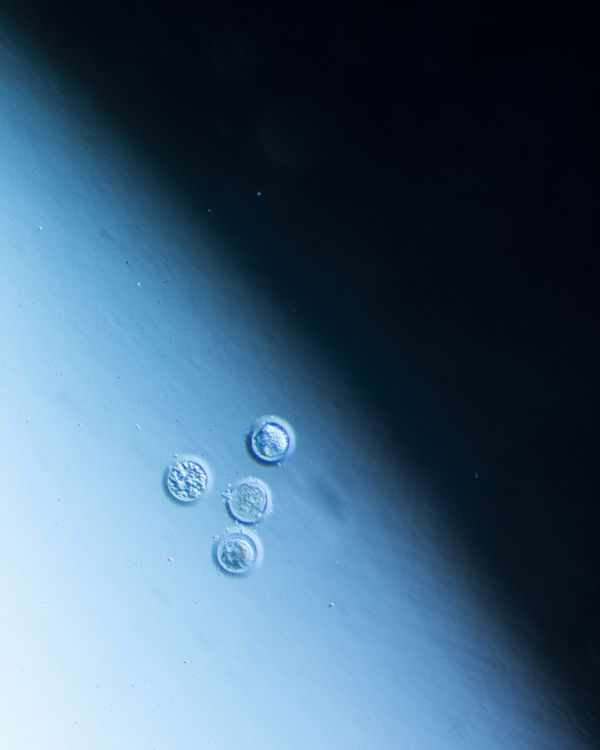

At the moment of fertilization, the egg releases chemical signals that attract the ideal spermatozoid, the most compatible, to its center. Over the next two weeks, by some inexplicable chance, it’s possible that the fertilized egg will divide into two exactly equal zygotes, and it’s at that moment that the gestation of monozygotic twins will begin, two beings with the same DNA chain and genetic information.

Las dos hebras (The Two Strands) seeks to understand, through history and metaphor, the other who is me, returning to that miniscule moment that gives way to my origin and that of my twin. I try to understand, decipher, and imagine it. My search has centered on the study of genetic history from the time of Pythagoras and that of the mystical sperm that gathers secret instructions on its journey throughout the body; on Aristotle who sustained that hereditary information was not found in the matter but in the message, like that of the drawings of the beaks of mockingbirds and Darwin’s tree of life. I have spent a great deal of time considering these events, recreating in my mind the human process for discovering oneself. I was accompanied by the work of Mendel, who obsessively cultivated and selected almost 400,000 seeds, hoping to find those that would produce identical descendants. I investigated the wet lab of Rosalind Franklin, British chemist and crystallographer, her life dedicated to science, and her discoveries that went unrecognized. Rosalind worked on deciphering the codes of nature, of crystals, and of invisible structures. She was the first to contemplate the image of an enigmatic molecule capable of containing hereditary information, what seemed to be the secret of life.

I traced the notes in Rosalind Franklin’s diaries, which review the power of images and how those images offer us answers. I used the answers from scientists from the second half of the twentieth century in regards to the nature of DNA, the molecule with 23 angstroms, as a metaphor, a bridge or a pathway in order to imagine and reflect on the nature of monozygotic twins. “DNA is made up of two interlocking chains arranged like the steps of a spiral staircase. The two strands contain the same information, except that they are in a complimentary position: each one is a reflection of the other. The most transcendental biological objects always appear in pairs.”1

In Las dos hebras, I combined archival images from the study of genetics, diagnostic images of my genes and those of my twin, photographs of monozygotic twins, microscopic photographs that were taken in science and fertility labs, and images with poetic symbols that, as a whole, seek to establish contact with other people, whether twins or not, who may arrive at a place to question what in this alphabet, reflexive code, or mirrored code makes us human.